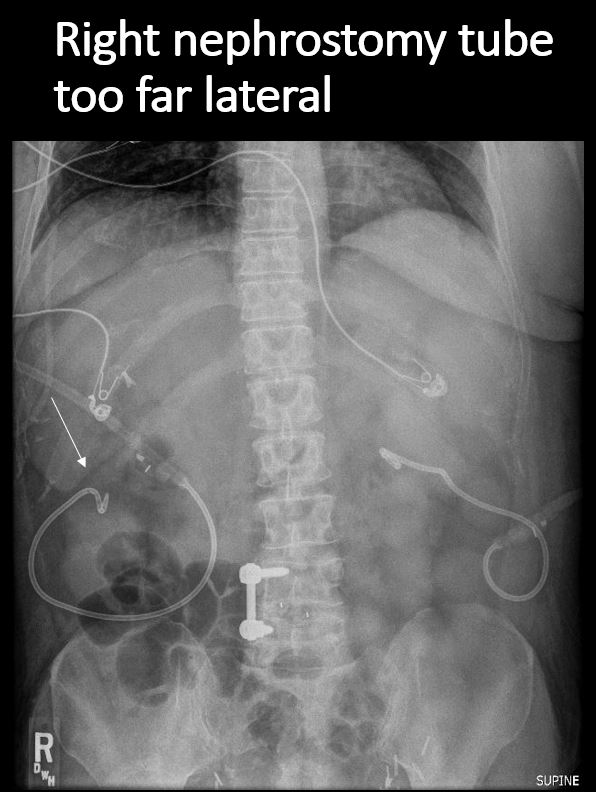

There is/are nephrostomy tubes, ureteral catheters, or a Foley catheter in place, and properly positioned. [Yes/No]